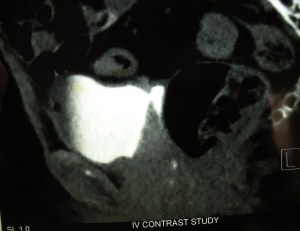

12.4.14 Presented a case of ‘mesenteric fibromatosis’ in the clinical meeting held in the medical education cell of the college. An 11 years old child was shifted from paediatrics ward, with a history of fever but was found to be having a big palpable mass in the right iliac fossa. A CT scan showed a 10 cm big well-defined mass in the peritoneal cavity. At operation, the mass was found to be arising from the mesentery of the distal ileum. The mass and the adherent loop of ileum were resected. Biopsy revealed an aggressive fibromatosis of the mesentery.

Mesenteric fibromatosis presenting as a diagnostic dilemma: a rare differential diagnosis of right iliac fossa mass in an eleven year old-a rare case report.Mahajan A1, Singh M1, Varma A1, Sandhu GS1, Singh M1, Nagori R1.

Journal of Clinical and Diagnostic Research. 2015 Nov, Vol-9(11): PJ01-PJ02